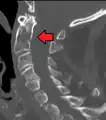

Fractures of the dens, not to be confused with Hangman's fractures, are classified into three categories according to the Anderson Alonso system:

- Type I fracture - Extends through the tip of the dens. This type is usually stable.

- Type II fracture - Extends through the base of the dens. It is the most commonly encountered fracture for this region of the axis. This type is unstable and has a high rate of non-union.

- Type III fracture - Extends through the vertebral body of the axis. This type can be stable or unstable and may require surgery.

A fracture of the base of the dens as seen on plain X-ray

A fracture of the base of the dens as seen on CT